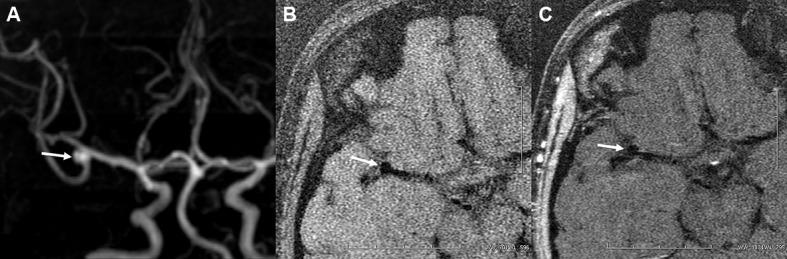

91 consecutive patients with 106 IAs were reviewed from February 2016 to April 2017. Patients and IAs were divided into ruptured and unruptured groups. In addition to the clinical characteristics of the patients, the features of IAs (eg, shape) were evaluated by CT angiography, whereas wall thickness, enhanced patterns, and enhancement ratio (ER) were evaluated by MRI. Multiple logistic regression analysis was used to identify independent risk factors associated with the rupture of IAs. Receiver operating characteristic curve analysis was performed on the final model, and the optimal thresholds were obtained.

ER (OR 6.638) and partial wall enhancement (PWE) (OR 6.710) were not markers of aneurysms more prone to rupture, but simply were more commonly found in the ruptured aneurysm cohort. The threshold value for ER was 61.5%.

ER (≥61.5%) and IAs with PWE are better predictors of rupture. Increased attentions should be paid to these factors during assessment of IA rupture.